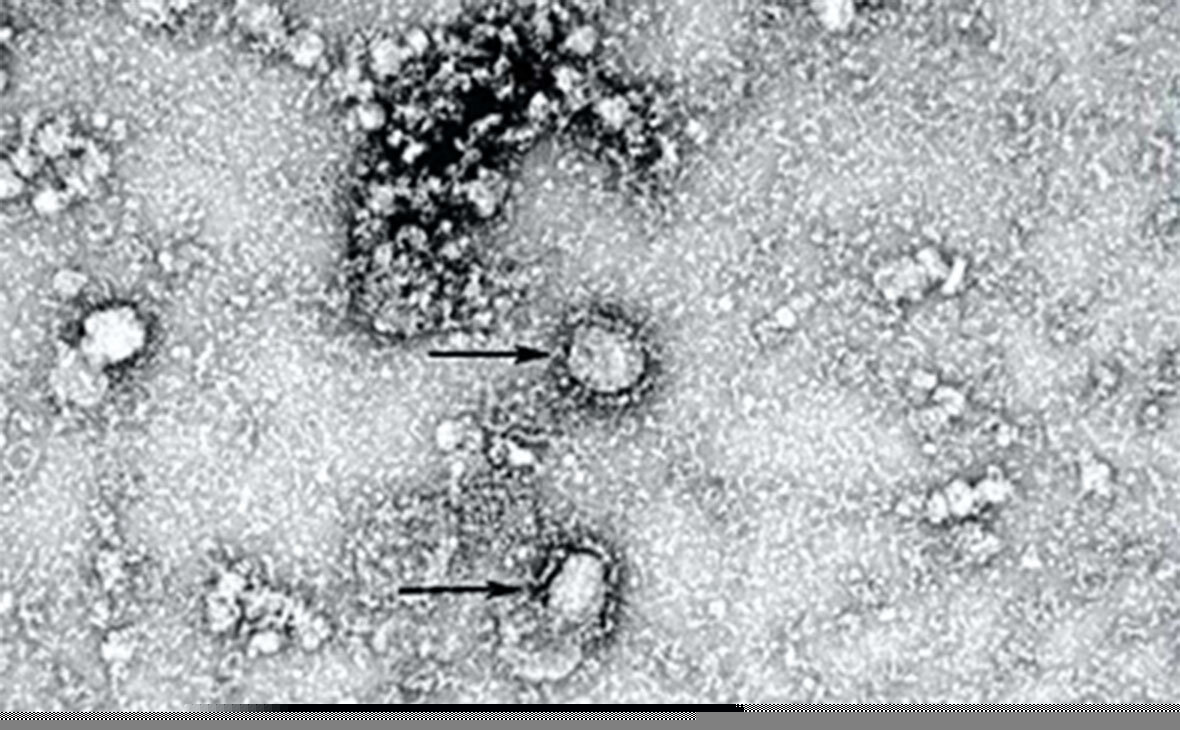

Коронавирусы под микроскопом

Коронавирусы (лат.Coronaviridae) — это семейство вирусов , включающее на январь 2020 года 40 видов РНК-содержащих вирусов, объединённых в два подсемейства, которые поражают человека и животных. Название связано со строением вируса, шиповидные отростки которого напоминают солнечную корону . Назначение «короны» у коронавирусов связано с их специфическим механизмом проникновения через мембрану клетки путём имитации «фальшивыми молекулами» молекул, на которые реагируют трансмембранные рецепторы клеток. После того как рецептор захватывает фальшивую молекулу с «короны», он продавливается вирусом в клетку и за ним РНК вируса входит в клетку.